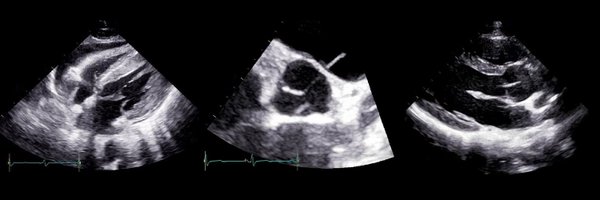

100% endorse. In 2022 it's difficult to justify not having 24/7 access to basic echocardiography in all acute settings.

How do we improve the UK care of cardiogenic shock? Patients need networked care, access to accredited echocardiographers and a shock MDT — 24/7. Clinicians need to have the skills to spot CS and know how to call Ghostbusters #SOA22